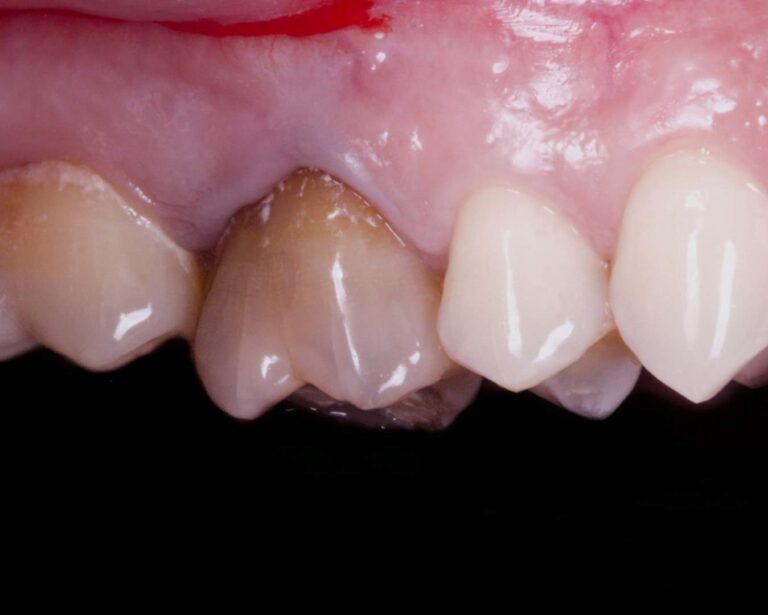

Cirurgia apical para remoção de quisto